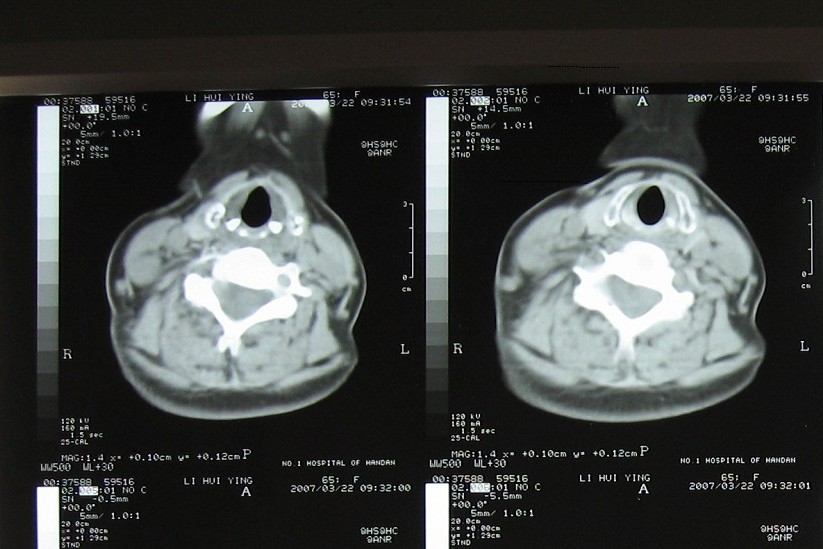

支持考虑:神经原性肿瘤。(右侧椎间孔扩大,椎板破坏,局部明显的软组织肿块,并与椎管 神经根关系密切。)

支持考虑:神经源性肿瘤(右侧椎间孔扩大,椎板破坏,局部明显的软组织肿块,并与椎管神经根关系密切)。